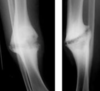

Qué fracura antebrazo se observa?

Monteggia Fx cúbito proximal + luxación radio prox ( n. interoseo posterior ) la Cabra tira al MONTE

62

Galeazzi Fx radio distal + luxación cúbito distal JALEA Real